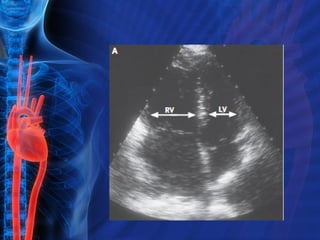

Ecocardiograma 30 a 40% pacientes presenta alteraciones Aumento del tamaño ventricular derecho Disminución función ventriculo derecho Regurgitación tricuspidea Disfunción ventricular derecha y trombo ventricular derecho implicados en el pronostico

Ecocardiograma En TEP Diagnóstico : Embolo en Cavidades derechas Evalúa la repercusión hemodinamica Dilatación Ventricular derecha Hipertensión Arterial Pulmonar Movimiento paradojico del septum interventricular

Ecocardiograma 30 a40% pacientes presenta alteraciones Aumento del tamaño ventricular derecho Disminución función ventriculo derecho Regurgitación tricuspidea Disfunción ventricular derecha y trombo ventricular derecho implicados en el pronostico

Ecocardiograma En TEPDiagnóstico : Embolo en Cavidades derechas Evalúa la repercusión hemodinamica Dilatación Ventricular derecha Hipertensión Arterial Pulmonar Movimiento paradojico del septum interventricular